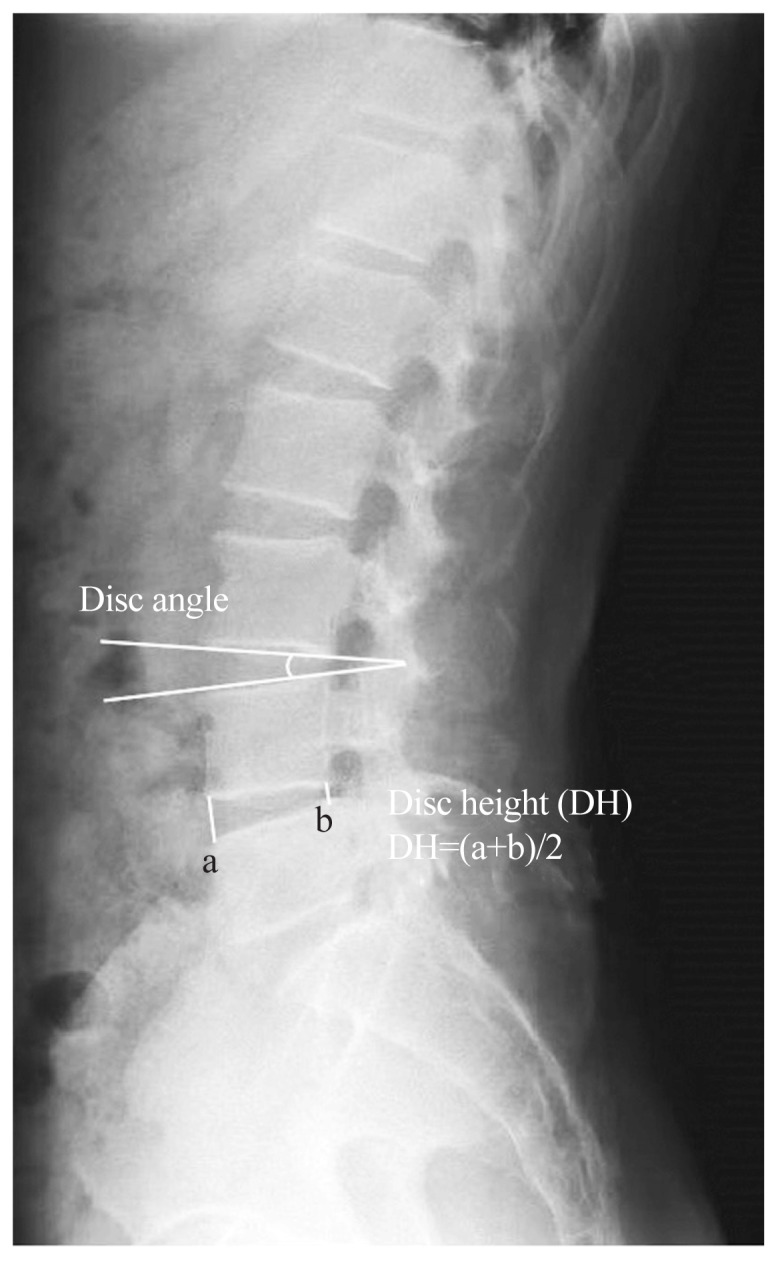

Results: The mean operative time in the UBE group (86.1±11.4 minutes) was significantly longer than in the open microdiscectomy group (72.3±8.0 minutes, p=0.032). UBE was associated with significantly lower estimated blood loss (54.1±13.7 mL vs. 92.5±11.6 mL, p=0.001) and shorter hospital stay (3.7±1.2 days vs. 6.6±1.4 days, p=0.001). The mean VAS score for back pain at 1 week was significantly better in the UBE group (1.88±0.60 vs. 3.59±0.72, p=0.004). However, both surgical techniques showed similar long-term results regarding disc height, disc angle changes, and patient-reported outcomes.